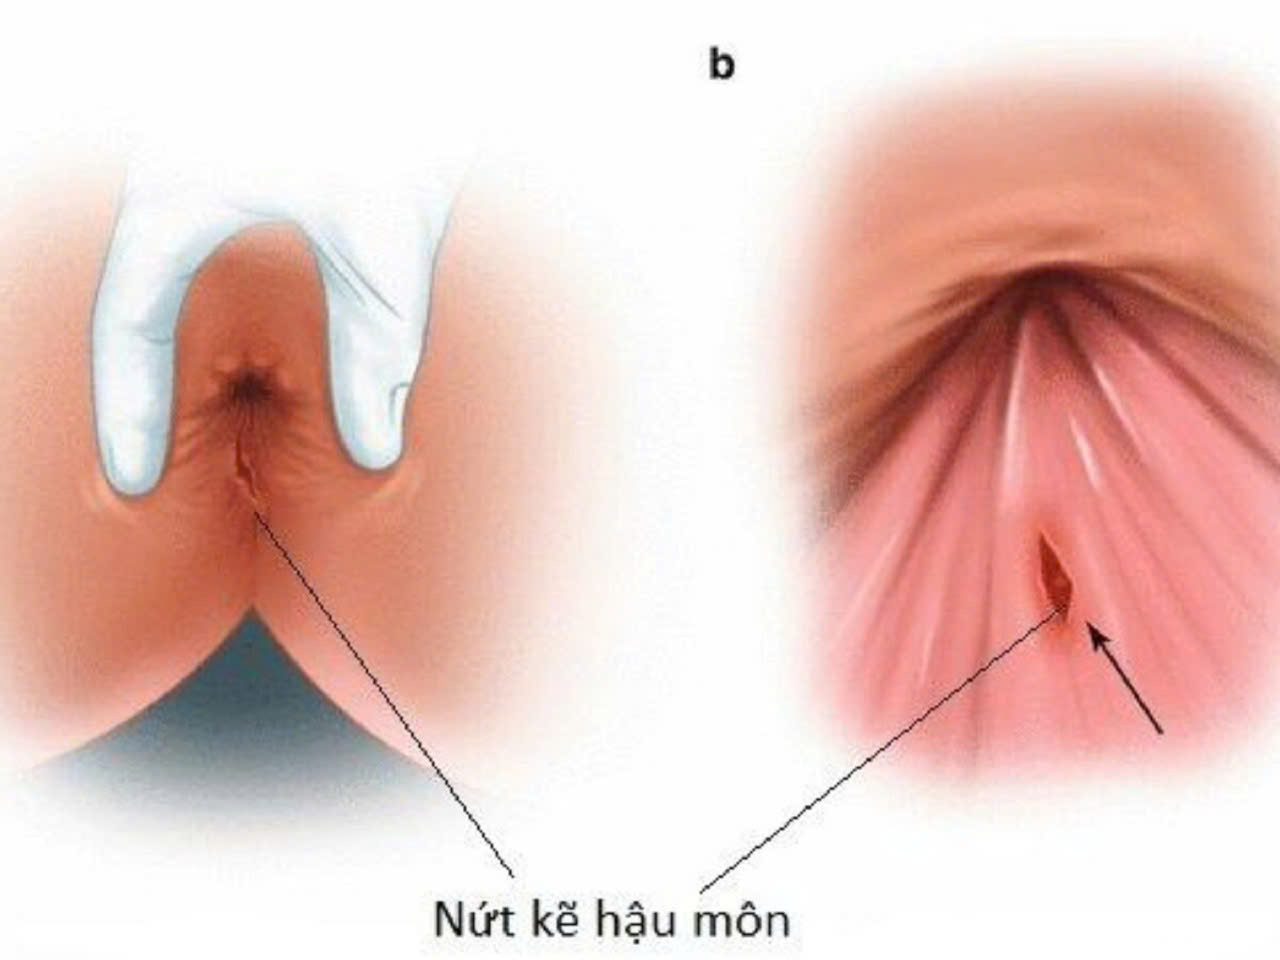

Biến chứng của táo bón bệnh nứt hậu môn

Táo bón kéo dài không chỉ gây khó chịu mà còn dẫn đến những tổn thương nghiêm trọng, điển hình là nứt hậu môn . Khi phân trở nên khô và cứng, cố gắng đi rặn mạnh để đi ra ngoài làm hậu môn bị tổn thương dẫn đến vết rách trên mô lót ở hậu môn. Tổn thương này sẽ gây đau, chảy máu, khiến người bệnh càng khó khăn và đau đớn mỗi khi đi vệ sinh, dẫn đến tình trạng táo bón càng trầm trọng hơn.

Triệu chứng nứt hậu môn

- Đỏ, đau rát khi đi bảo vệ sinh: Người bệnh đau thấy đau nhói, khó chịu mỗi lần đại tiện, đặc biệt là khi phân khô cứng.

- Chảy máu: Máu tươi có thể xuất hiện trên giấy vệ sinh hoặc xen kẽ trong phân.

- Vết nứt rõ ràng: Có thể quan sát thấy một đường nứt nhỏ xung quanh khu vực hậu môn, hậu môn bị sưng tấy, cảm giác đau mỗi khi sờ vào